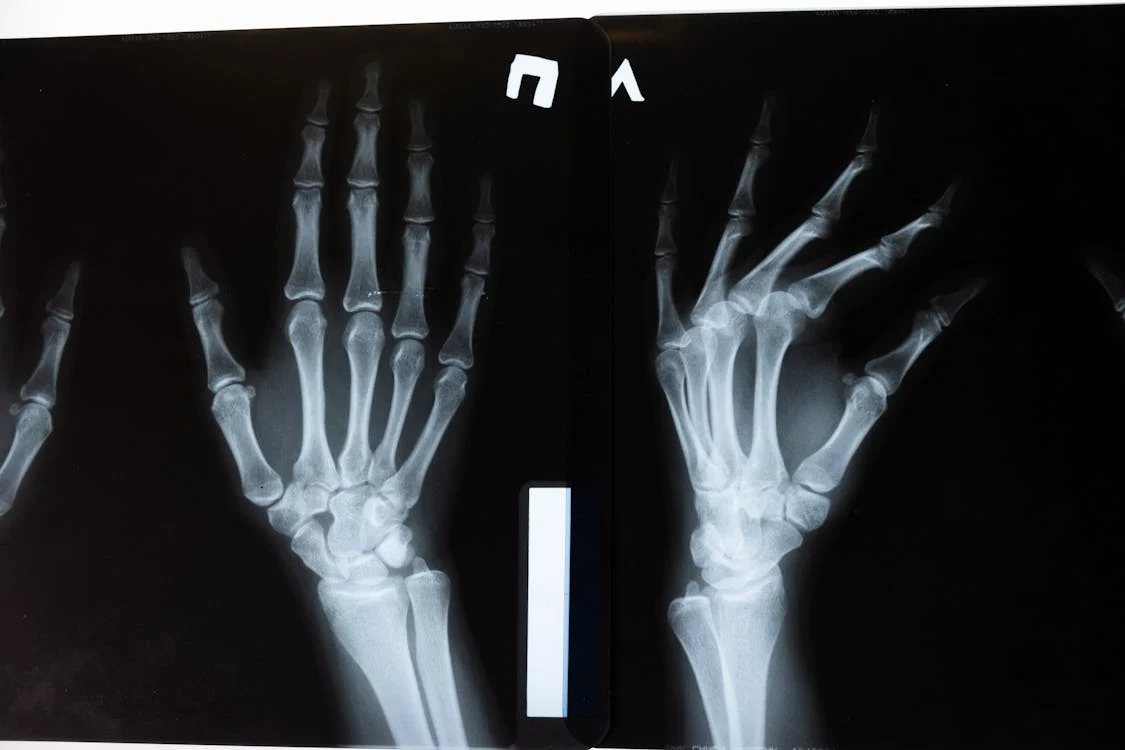

손목터널증후군은 손목의 정중신경(median nerve)이 압박되어 발생하는 신경질환입니다. 손목에는 여러 힘줄과 신경이 지나가는 좁은 통로(수근관, Carpal Tunnel)가 있는데, 이곳이 좁아지거나 내부 압력이 높아지면 정중신경이 눌리면서 손 저림과 통증이 나타납니다.